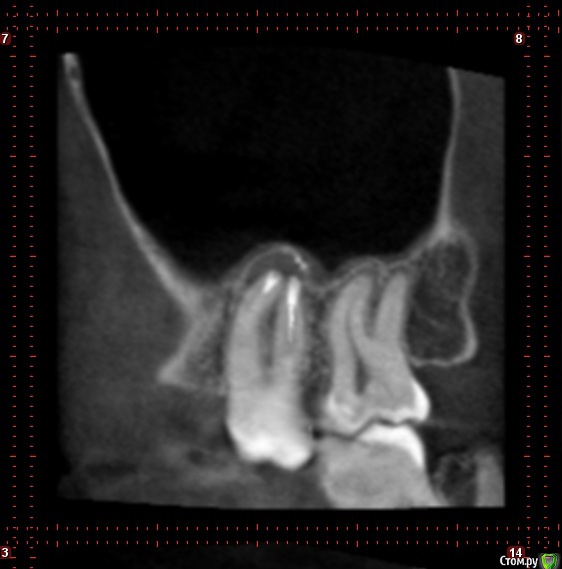

Seven Опубликовано 4 февраля, 2019 Поделиться Опубликовано 4 февраля, 2019 ЗдравствуйтеЗуб на верхней челюсти, справа, перед зубом мудрости.Зуб, лечился с удалением нервов лет 5 назад. Сейчас на протяжении пару месяцев чувствовалось распирание и жжение, перед этим между ним и зубом мудрости часто попадала пища и я чувствовал болезненность.фото, оно большое https://b.radikal.ru/b42/1902/18/ad6fa98f7463.jpgДве недели назад пошел к зубному. Определили на корне этого зуба кисту фото 12,13 в зеленой рамке, 8 в красной. Врач прочистила канал и заложила лекарство, под временную пломбу. Прочистка пошла не совсем по плану, инструмент пошел по красной линии на рисунке(по мотивам того что я видел на ренгене), врач сказала раз крови нет значит в кость не попали. Да под зубом есть уплотнение на десне, до введение лекарства было довольно болезненное, теперь намного меньше. Собственно теперь проблемы, прошло две недели, и две недели этот зуб у меня болит, причем собственно сам зуб не очень, болит чуть выше него, от ноющей до очень сильной боли, вместе с ним болит голова, и глаза, отдает немного в ухо. Сильная боль радует меня по ночам и утрам. По совету врача пью Нимесил, помогает, но без него продолжает болеть. Так и должно быть ? или что то идет не так ? Врач неделю назад на приеме говорила надо наблюдать, но т.к. он меня очень беспокоит решил дополнительно спросить у Вас. Насколько вероятно развитие осложнений в моей ситуации, если время пользуясь обезбаливающими побегать по другим врачам ? Или бежать вырывать ? Если вырывать то случай простой, или искать врача поопытнее/подороже ? Начитался интернетов, что у меня корень зуба в гайморовой пазухе, может быть осложнение =) да и киста. Ссылка на комментарий